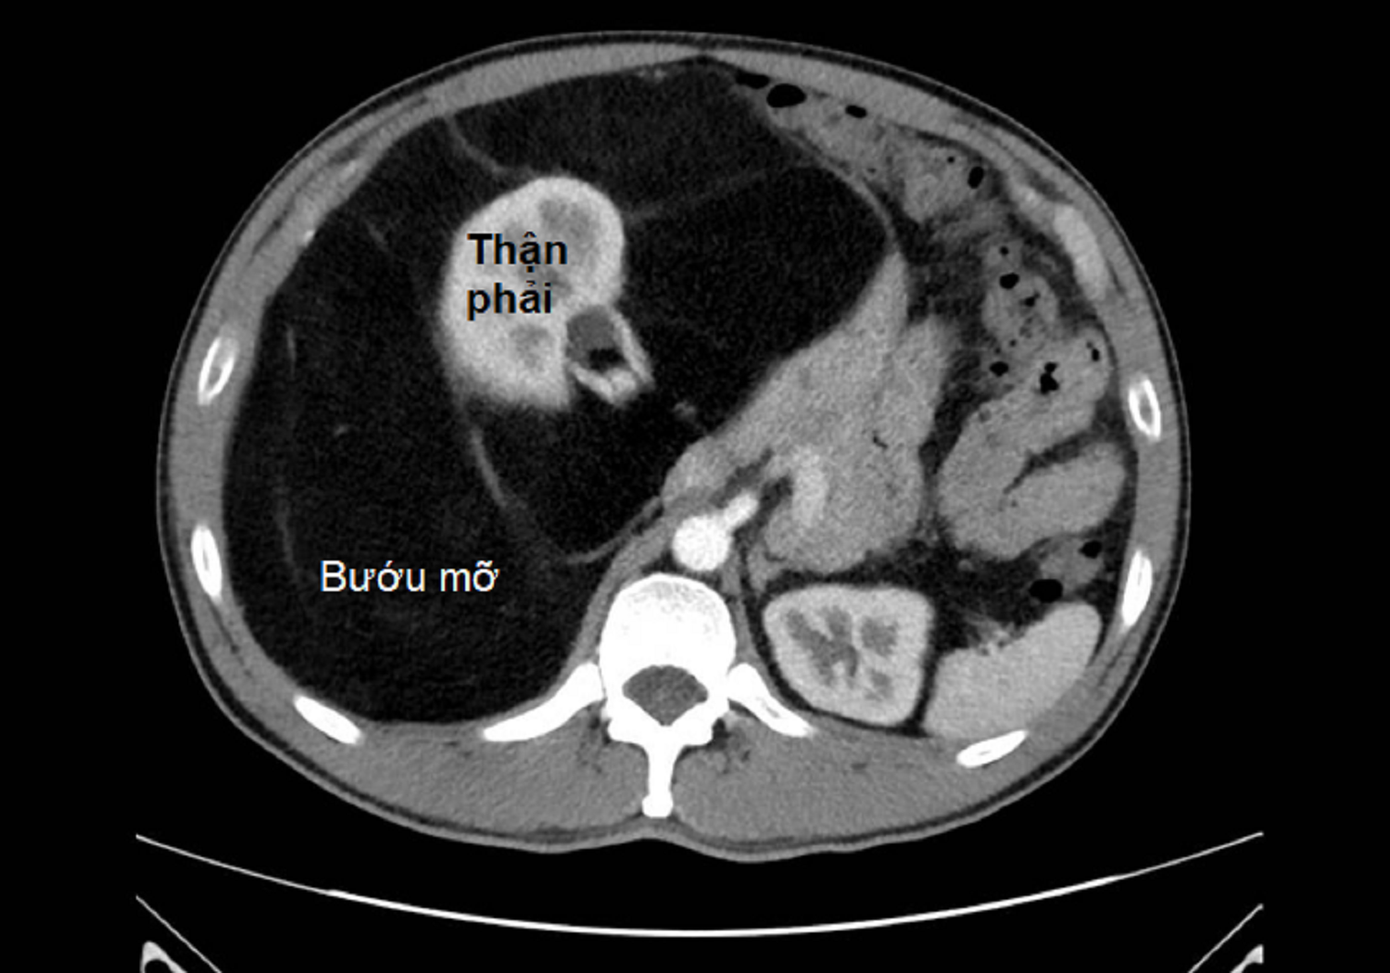

| Hình ảnh kiểm tra ghi nhận khối bướu mỡ khổng lồ chiếm gần hết ổ bụng bệnh nhân |

BS-CKII.Nguyễn Phúc Minh – Trưởng khoa Ngoại Tiêu hóa, Bệnh viện Bình Dân cho biết, bệnh nhân mang một khối bướu mỡ hiếm gặp, có đường kính tới 40 cm. Khối bướu quá lớn đã đè ép thận phải và chèn lên nhiều mạch máu lớn trong bụng.

“Khối bướu dính chặt vào các cấu trúc mạch máu như động mạch, tĩnh mạch chủ bụng, đòi hỏi phẫu thuật hết sức tỉ mỉ để vừa lấy sạch bướu vừa bảo tồn chức năng thận” - BS.Phúc Minh nói.